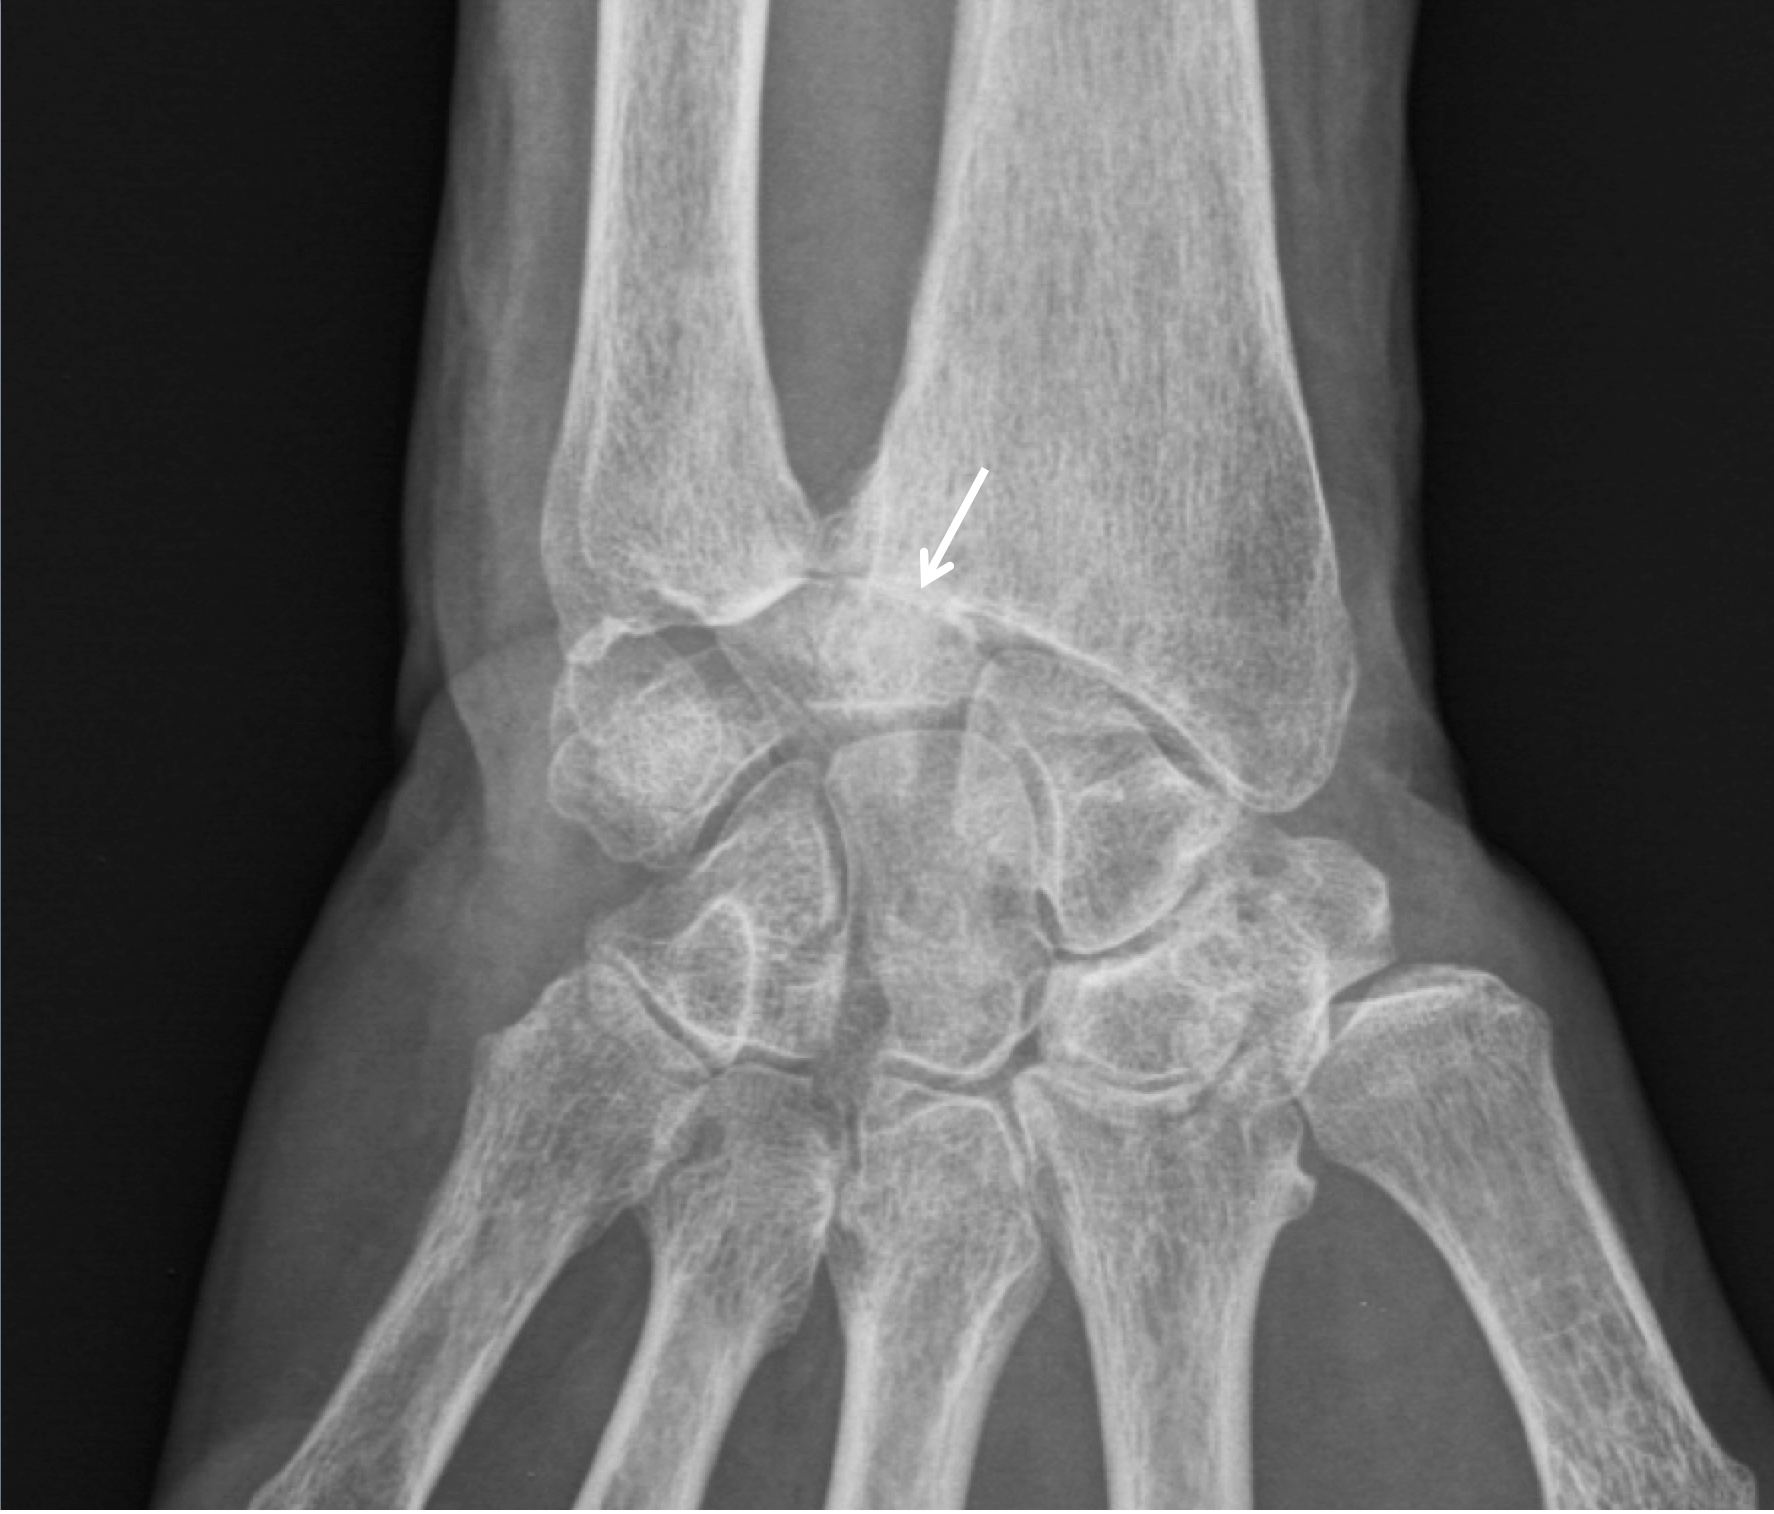

Les atteintes ligamentaires peuvent être sources méconnues de douleur chronique du poignet. Après un traumatisme initial parfois oublié, les patients développent des douleurs mécaniques avec plus rarement des claquements ou des sensations d’instabilité et de lâchage d’objets.. L’index radio-ulnaire inférieur (IRU) mesure la légère différence de longueur normalement observée entre radius et ulna.. Sur un poignet normal, sa valeur moyenne est de 47° (avec un écart normal assez large de 30 à 60°).. Le rayon directeur est droit et les avant-bras sont soulevés de 20 à 30° du plan de la table. + Profil :